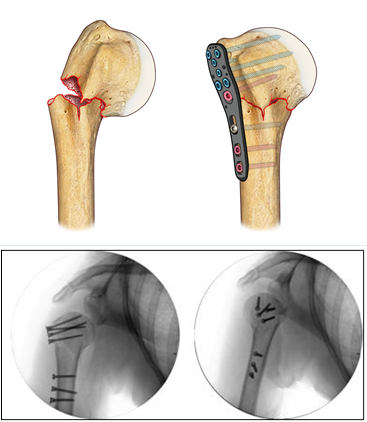

Hardware for traumas was also developed (endomedullary systems, more resistant and better contoured titanium plates, which provide an improved strength of the screw-bone and screw-plate interface, plates made of xray-transparent plastic material, fig. 4), up to providing bioreabsorbable screws, useful in some rare articular fracture.

In most severe cases, when it is not possible to reduce and fix the elbow intra-articular fracture, a prosthesis substitution (of the joint humeral part) and a synthesis with plates and screws can be necessary, contemporarily, within the same surgical session.

Nonunions or malunions are often treated with associating metal plates with bone grafts (from donors) and growth factors (platelet gel produced from the patient’s blood), thanks to the presence, within the Institute, of the transfusion service and the Musculoskeletal Tissue Bank.